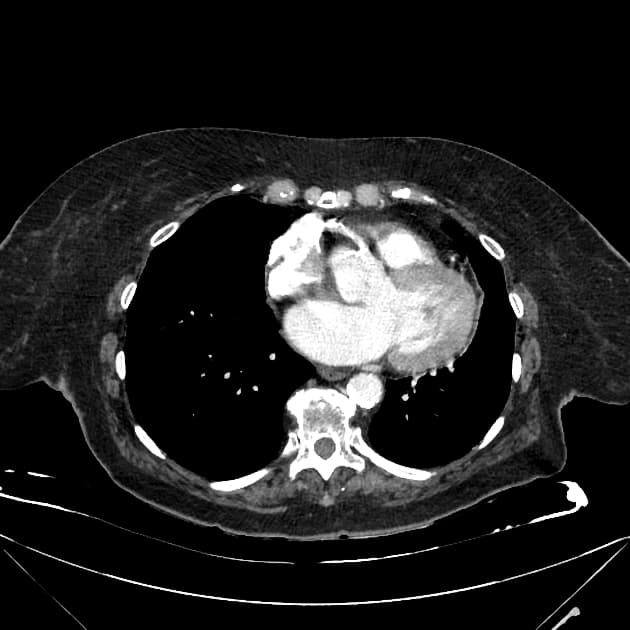

- Có giãn dạng thoi các ống mật ngoài gan (bao gồm ống mật chủ và ống gan chung) chứa nhiều ổ giảm tín hiệu trên mọi chuỗi xung, phân bố theo trọng lực, phù hợp với hình ảnh sỏi.

- Không có giãn đường mật trong gan.

Interpretation: U nang ống mật chủ (type 1) kèm theo tổn thương IPMN nhánh bên phát hiện tình cờ (incidental side branch IPMN).

U nang ống mật chủ - type I (choledochal cyst - type I)